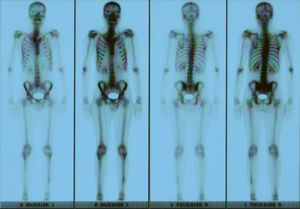

Clinical presentationA 42-year-old male with no prior history presented 3 months prior to his coming to our department with continuous pain in the middle third of the left leg. Upon examination there was selective pain on palpation on the mid third of the left tibia. No skin atrophy or deformity of the affected limb was detected. Laboratory analysis, including acute phase reactants, complete blood count, blood chemistry, bone remodeling markers in blood and urine, thyroid hormone and proteins, were normal. A simple X-ray of the left leg (Fig. 1) presented an image of hyperostosis with a thickened cortex on the mid third of the tibia and peroneus, extending along the bone and showing a “dripping candlewax” image. A bone scan with 99Tc (Fig. 2) observed an increase in uptake. A computerized tomography (Fig. 3a and b), showed dense cortical hyperostosis of the distal half of the tibial and peroneal diaphysis, with wavy and exhuberant borders, cortical sclerosis and periostic and endostic thickening, predominantly on the lateral tibia and mid peroneal, with a “dripping candlewax” aspect, suggestive of melorheostosis.

DiscussionWe present this case because of the low incidence of the disease and on differential diagnosis doubts raised with other processes such as osteomyelitis or tumors. When it affects long bones it is usually diagnosed by the characteristic “dripping candlewax” image. To safely differentiate from neoplastic or infectious processes, a bone biopsy and microbiological cultures of samples of affected tissue must be performed (although they are not required for the diagnosis of melorheostosis). The disease can occur at any age, although the incidence is higher in the second and third decades of life. In fact, in terms of age of onset, in some series up to 50% of cases of the disease appear before 20.3 It may be asymptomatic for a long time, but the most common clinical manifestations are: (a) sclerotic changes confined to an extremity; (b) altered contour of the affected bone and even permanent development of genu varus or valgus deformities of the lower limbs; (c) pain, which is often intense, and (d) limitation of motion in joints formed by the affected bone. Alteration of skin pigmentation in the affected area is unusual, but in some cases sclerodermatous linear lesions appear (some authors have called linear scleroderma melorheostic) and skin changes seem to be representative of the proliferative disorder that causes hyperostosis. The presentation in the axial skeleton is rare but may be accompanied by severe nerve4 root involvement. The condition may be monostotic or polyostotic,5 affecting one or more bones of the limb, and the disorder affects the lower limbs more frequently, starting proximally and moving distally. The lower extremities are affected more often than the upper ones.6 Although rare, it may be associated with renal (artery stenosis), and vascular abnormalities (hemangiomas, arteriovenous malformations, aneurysms, varicose veins), lymphatic system disorders (lymphedema, lymphangiectasia) and tumors (lipomatous and desmoid tumors). Its etiology is uncertain (it is hypothesized that these alterations are a result of the same disorder, as vascular mesenchymal dysplasia). Recent studies suggest that it may be due to a mutation in the LEMD3 gene, which encodes a nuclear membrane protein involved in Smad signaling system. This mutation is also involved in the pathogenesis of osteopoikilosis and Buschke-Ollendorff syndrome (an autosomal dominant disorder that presents clinically with elastic nevi and osteopoikilosis).7 The diagnosis is usually performed by imaging techniques (radiography, CT, MRI and bone scans). When it affects the long bones it is typically characterized by a “dripping candlewax”8 image. A bone scan may help differentiate melorheostosis from other processes, such as osteopoikilosis and striated osteopathy, in which there is no increase in uptake. Laboratory tests showed normal levels of calcium, phosphorus and bone alkaline phosphatase. The differential diagnosis must include entities such as osteopetrosis, osteopoikilosis, striated osteopathy, infantile cortical hyperostosis and osteomas. The disease is a benign entity with a generally chronic course and periods of exacerbation and remission. There is no specific treatment. Therapy is symptomatic and aimed at controlling bone pain.9 In some cases, good results were obtained with infusions of pamidronate.10 In cases with significant bone deformity or soft tissue involvement, corrective surgical treatment may be appropriate.